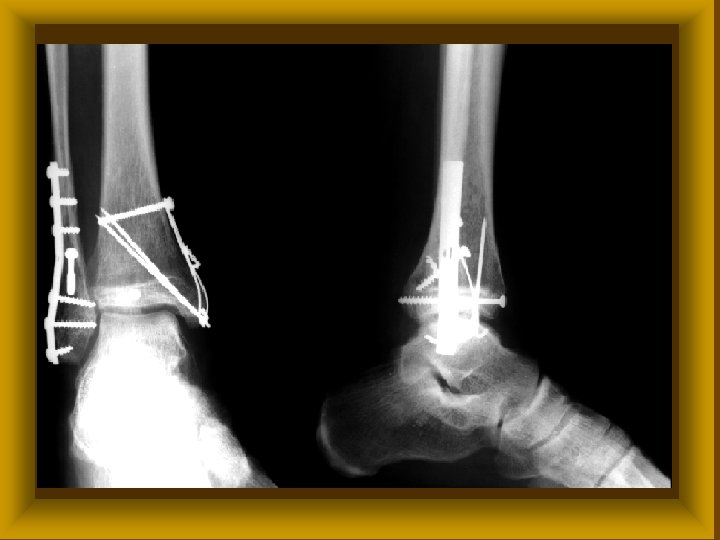

FRACTURA KEZELÉSE II Ø Elsősegély Ø Sebészi ellátás * repositio * rögzítés • gipszkötések • extensio • osteosyntesis Ø Rehabilitáció

FRACTURA KEZELÉSE III Osteosynthesis Ø Csavaros osteosynthesis Ø Lemezes osteosynthesis Ø Velőűrszegezés Ø Dróttűzés Ø Dróthurok Ø Fixateur externe

FRACTURA KEZELÉSE IV Osteosynthesis idikációi Műtét nélkül ritkán gyógyuló sérülések (patella) Ø Nyílt törések Ø Interpositummal járó törések Ø Ideg, érsérüléssel járó törések Ø Hosszú csövescsontok instabil törései Ø Epiphysis törések gyermekkorban Ø